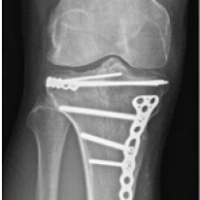

An 87-year-old female with a medical history of dementia, hypertension, and hyperlipidemia underwent a left THA through a posterior approach in 2010. She presented to the emergency department following a ground-level fall, reporting severe left hip pain and an inability to bear weight. Imaging confirmed a left periprosthetic hip dislocation (Fig. 1).

Figure 1: Pre-reduction X-ray of left hip.